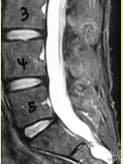

Investigations included MRI of the Lumbosacral spine which showed a large Tavlov Cyst at S1 on the right and S2 on the left. There was no bony erosion.

MRI of the cervical gland thoracic spine showed no neural compression. MRI of the right thigh and hip showed mild hip effusion but was otherwise normal.